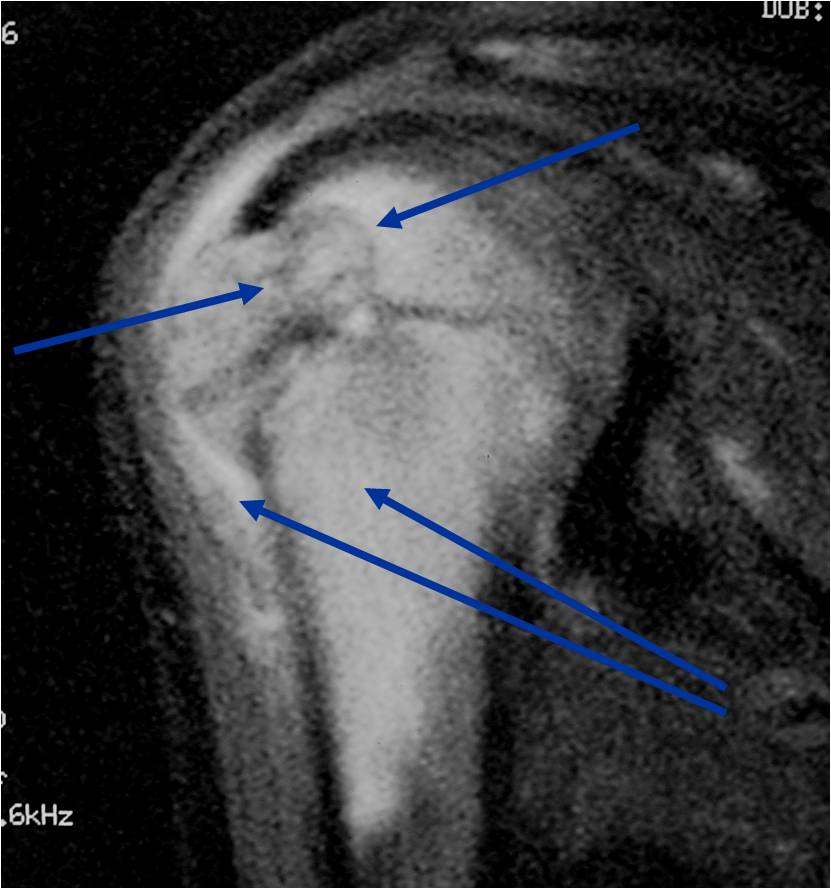

- (MRI appearance)

- Geographic, well circumscribed lesion in the epiphysis

- Intermediate Signal on T1

- High signal on T2 mixed with low signal areas (low signal areas proposed to be secondary to lysosomal content of highly cellular areas)

- Fluid/Fluid levels demonstrated in tumors that have undergone ABC change (aneurysmal bone cyst change)

- Extensive Surrounding edema is common

- Joint effusion in 30-50% of cases